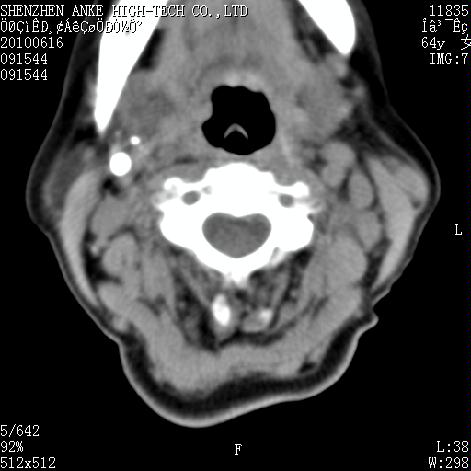

标题: CT27132:患者女,64岁,颈部及全身多处包块,现觉吞咽困难4 [打印本页]

标题: CT27132:患者女,64岁,颈部及全身多处包块,现觉吞咽困难4

右侧甲状腺癌伴右颌下腺淋巴结转移

右侧甲状腺癌伴淋巴结转移

淋巴瘤可能,再向下扫描胸部看纵隔内淋巴结

右侧甲状腺癌伴右颌下腺淋巴结转移!建议增强!